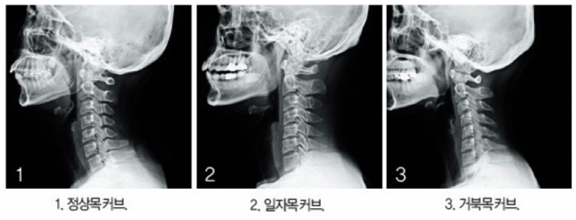

우리 목은 7개의 뼈로 구성되어 있고 앞쪽으로 볼록하게 휜 알파벳 C자 모양으로 되어 있는 게 정상이다.하지만 목을 길게 빼고 눈높이보다 낮은 화면을 지속적으로 보고, 장시간 나쁜 자세로 생활하면 목뼈의 모양이 C자형에서 일자모양으로 뻣뻣해지는 데, 이를 거북목 증후군이라 부른다. 또한 거북이처럼 얼굴은 앞으로 나오고 어깨와 등이 구부정하게 말리는 증상도 함께 나타난다.